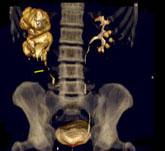

问题 男,58岁,尿频,尿痛伴低热乏力2月,CT如图所示,下列说法正确的是 ( )

选项 A、左侧输尿管结核 B、左侧输尿管癌 C、左侧输尿管多发性狭窄 D、左侧肾结核 E、左侧肾盂肾盏扩张,其边缘不整

答案 ACDE